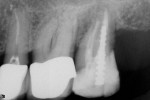

Her clinical examination showed porcelain-fused-to-metal crowns in place on teeth Nos. 3 through 5 and a core in place on tooth No. 2. Examination of the margins showed a possible opening on the mesial of tooth No. 4. A radiographic examination revealed root canal treatment had been completed on teeth Nos. 2 and 5, ruling out these teeth as a cause of pain to thermal changes. The patient’s stated specific complaint was pain on exposure to a hot cup of coffee that cold water relieved. She could not identify a specific tooth as the source of the problem.

Using this diagnosis by exclusion with the intraligamentary injection leaves a lot of anxiety behind. Once it is established that hot liquid generates the pain, the clinician can rule out a single tooth at a time. In this case, the author started with tooth No. 4. After he administered the PDL injection and waited a reasonable amount of time, he gave the patient more hot water. No pain was generated. He repeated this twice, as a way to demonstrate to the patient that the offending tooth had been “numbed” and, therefore, the generation of pain had been stopped. The diagnosis was made and the tooth was ready to be treated (Figure 2, Figure 3, Figure 4). The author believes diagnosis by anesthetic exclusion using the STA System Injection Technique will gain in popularity as practitioners become more comfortable with the STA system and techniques.